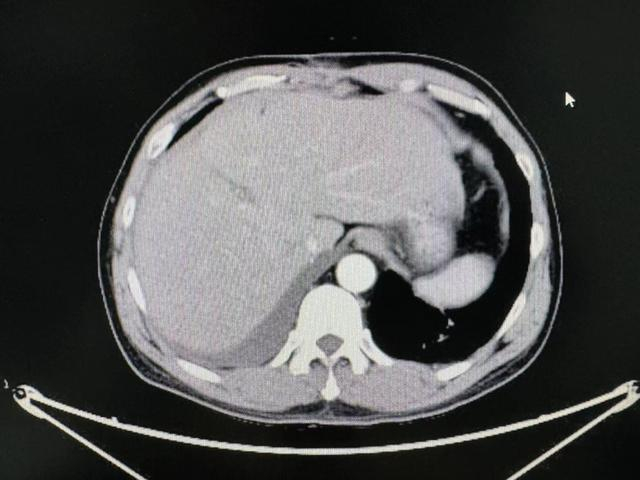

在住院期间,患者查上腹部CT后提示肝左右叶交界处肝癌,经同济医院肝胆外科中心主任谭蔚锋会诊后进行后续治疗。

术前影像学资料

1月4日行腹腔镜下特殊肝段切除术(肝中叶IVA+VIII段),术中病理为肝细胞癌。